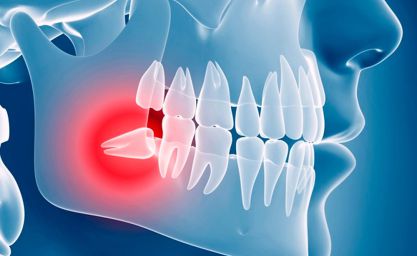

- Falta de espacio en la arcada

La muela estaría presionando y ocasionando continuas molestias - Retención por ángulo incorrecto

Presiona el resto de dientes y produce desalineación - Erupción parcial

Tanto la falta de espacio como el ángulo incorrecto pueden provocar la erupción parcial, quedando una parte de la muela dentro de la encía, siendo susceptible a infección

Lo que va a determinar realmente que se decida por la exodoncia serán una serie de beneficios que aporten bienestar al paciente. De esta forma, extraer las piezas estaría justificado cuando estamos ante casos que provoquen infección, como la pericoronaritis recurrente, flemones y otros cuadros clínicos de infección odontogénica.